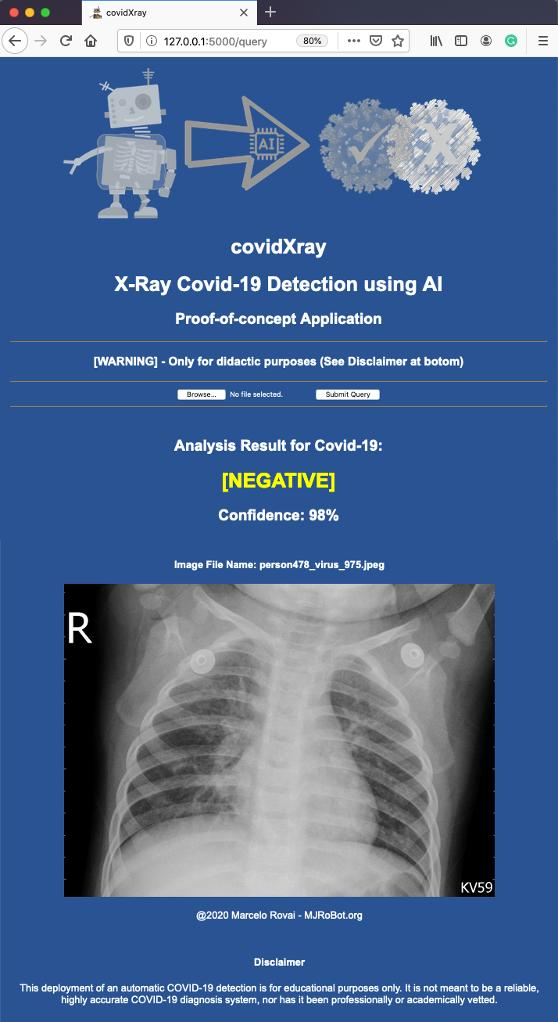

对其中一张有肺炎但没有Covid-19的图片重复测试:

结果是:(‘POSITIVE’, 96.0)

结果是:(‘NEGATIVE’, 99.0)

结果是:(‘NEGATIVE’, 98.0)